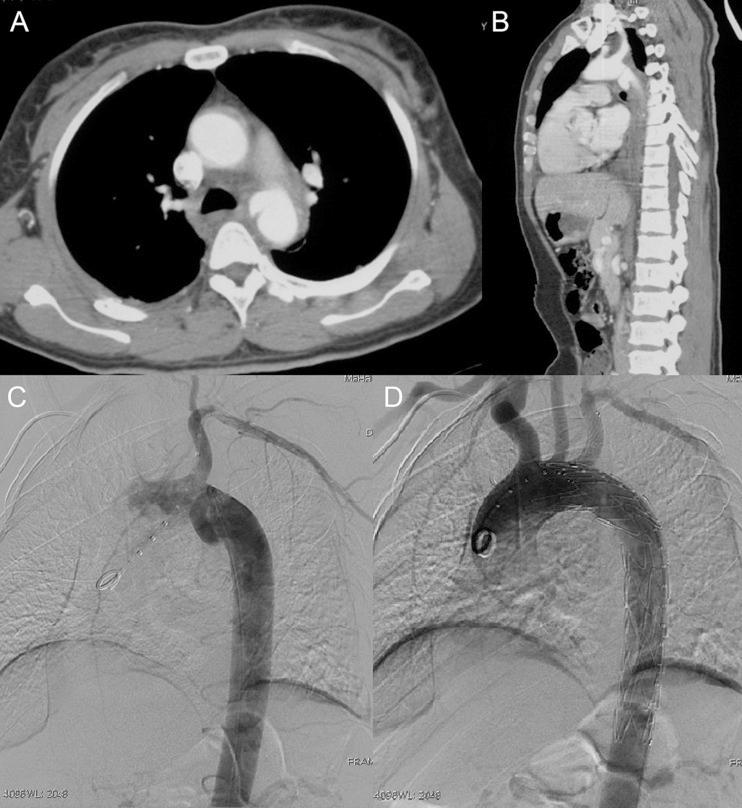

胸主动脉腔内修复术中保留左锁骨下动脉的烟囱技术。

The chimney technique for preserving the left subclavian artery in thoracic endovascular aortic repair.

The objective of the present study was to evaluate short- and mid-term outcomes of the left subclavian artery (LSA) chimney stent implantation (LSACSI) during thoracic endovascular aortic repair (TEVAR), and to summarize our experience with this technique.

METHODS

From June 2010 to September 2012, 59 patients (49 men; mean age of 57.4 ± 13.3 years, range from 26 to 83 years) who underwent TEVAR and LSACSI were enrolled. Patients suffered from Stanford type B aortic dissection (n = 27), penetrating aortic ulcer (n = 18), aortic arch aneurysm (n = 9), pseudoaneurysm of the aortic arch (n = 4) and proximal type I endoleak after TEVAR of aortic dissection (n = 1). Elective settings were performed in 72% and emergent in 38% of all patients. Follow-up was performed at postoperative 3 months, 6 months and yearly thereafter.

RESULTS

The technical success rate was 98.3% (58/59), and 69 thoracic stent grafts were used. Sixty-two chimney stents, including 55 uncovered and 7 covered stents, were implanted in 59 LSAs. The overall immediate endoleak rate was 15.3% (9/59); type I endoleak was observed in 5 patients and type II in 4 patients. The difference in the immediate endoleak rate related to the anatomy between the outer and the inner curvature was statistically significant (35 vs 4%, P = 0.018). Chimney stent compression was observed in 3 patients and another stent was deployed inside the first one. Perioperative complications included stroke (3.4%, 2/59) and left upper limb ischaemia (1.7%, 1/59). The median follow-up period was 16.5 (range 1-39 months). The mortality rate during follow-up was 5.4% (3/56). Complications during follow-up included endoleak [overall, n = 8 (14.3%, 8/56); type I, n = 5; type II, n = 3], retrograde type A aortic dissection (n = 1), collapse (n = 3, 5.4%) or occlusion (n = 2, 3.6%) of the chimney stent.

CONCLUSIONS

Short- and mid-term results showed that it is feasible to preserve the patency of the LSA in TEVAR with the chimney technique for thoracic aortic pathologies close to the LSA. However, TEVAR combined with LSACSI was not advocated for lesions located at the outer curve of the aortic arch due to a high possibility of endoleak.